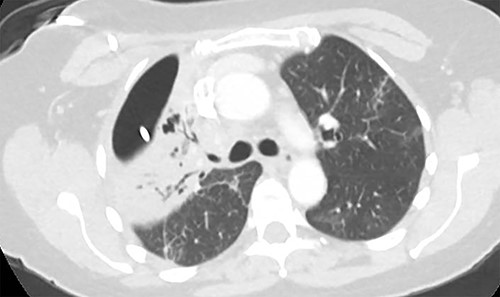

At the time of transfer, the patient was afebrile and hemodynamically normal, and she was not requiring supplemental oxygen. Her C-reactive protein level was 14.86 mg/l (reference <10) and white blood cell count was 8800 per mm3 (reference 4.5–10). Prior to transfer, her C-reactive protein level had been within normal limits. Computed tomography (CT) of the chest showed a residual pneumothorax (Fig. 2) and peripheral bronchopleural fistula (BPF). We treated her with open thoracostomy drainage (Clagett procedure), removing a segment of the second rib and suturing skin flaps to the thickened parietal pleura (Fig. 3). Due to institutional policy, no intra-operative images were obtained. On direct visualization, the visceral pleura overlying the upper lobe was thickened, but no frank purulence was noted. There was fibrinous exudate and air leak at two sites on the surface of the lung. A sample of the fibrinous tissue was sent to microbiology for clinical culture, which subsequently grew MSSA.

Axial image demonstrating right upper lobe consolidation and residual pneumothorax despite tube thoracostomy.